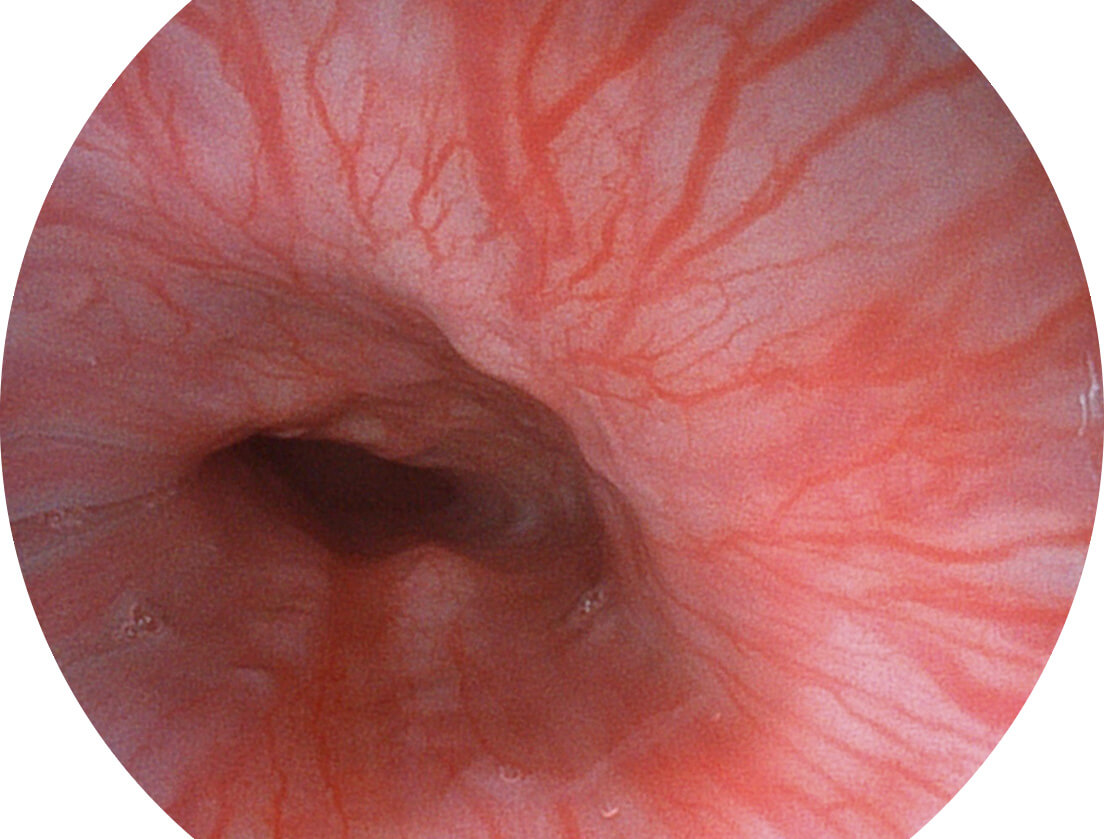

聚谱成像技术

Spectral Focused lmaging, SFI

图像具有高亮度、高黏膜血管颜色对比度的特点,且不改变粘液、食物残渣、粪便的基本颜色,可在中远景下进行观察,助力消化道早期疾病的诊断。

• 白光图像 SFI图像